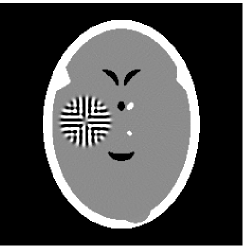

Furthermore, we used the classic ART iteration as the iteration operator in our numerical experiments. In order to compare the proposed superiorization algorithm with the classic superiorization algorithm, we applied the classic superiorization and -PP superiorization algorithm to two phantoms (see figure 1). The first one is the Shepp-Logan phantom[30], and the second one is the head phantom with a ghost which is invisible at 22 specified projection directions [10, 31]. In addition, we compare the performances of the two algorithms for the noiseless and noised data with different projections. In all experiments, the noised projection data was corrupted by additive Gaussian white noise with variance . We record the iterations, running time of program and mean square error (MSE) of different algorithms, where MSE is computed by

Noised projection data: For the noised projection data, the iteration processes were terminated when for 82 and 112 projections. The reconstruction images were given in Fig. 7. Table 4 showed the MSEs, iterations and running time of program of the results of images in Fig. 7.

|

|

| TV-S | TV-S |

|

|

| TV-PPS | TV-PPS |

By comparing the images in Fig. 6, 7 and numbers in Table 3, 4, we can obtain the same conclusions that the proposed perturbation can not only improve qualities of reconstructed images, but also can accelerate the convergent speed. However, we can observe that the reconstruction images suffer from artifacts regardless of the classic and the proposed algorithm when the projections is inadequate.